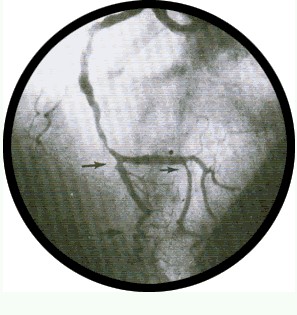

右前斜位:右冠状动脉 |

右冠状动脉象字母 “L” 1、右冠状动脉 2、右心室支 3、后降支

|